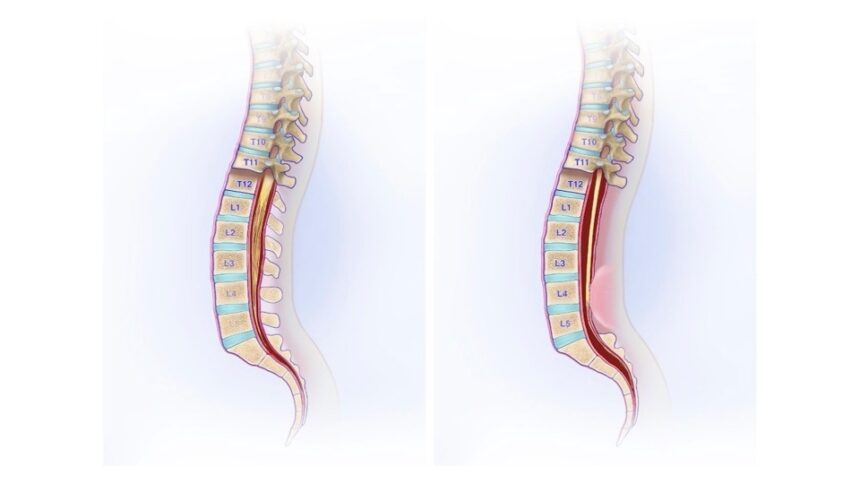

What Is Tethered Cord Syndrome?

It is a condition in which the lower end of the spinal cord is abnormally low and tightly attached within the spinal canal. It is usually a congenital developmental variation. It may also be referred to as a thickened filum terminale, fatty filum, or tethered cord.